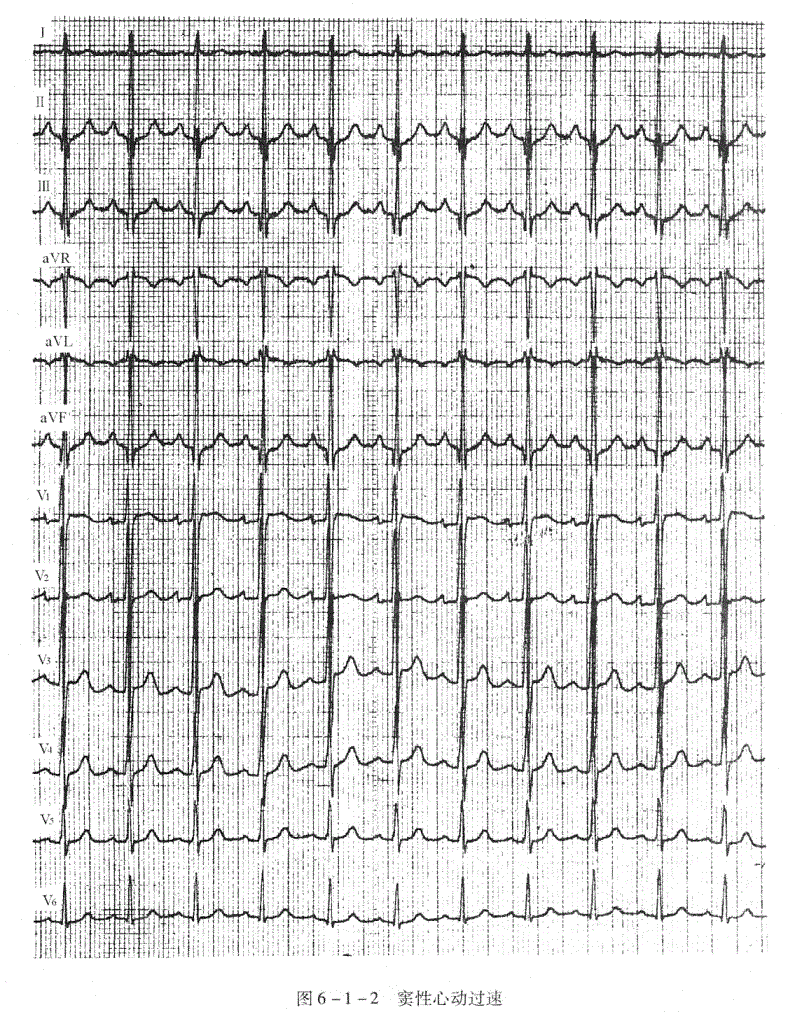

窦性P波,P波规律出现,P波在Ⅰ、Ⅱ、aVF、V

导联直立,aVR导联倒置,窦性心律的频率超过100次/分(图6-1-2)。

临床资料:男性,27岁。因感冒发热住院。

心电图分析:P波符合窦性。窦性心动过速,心率111次/分。其余各波段、间期均正常。

心电图诊断:窦性心动过速。